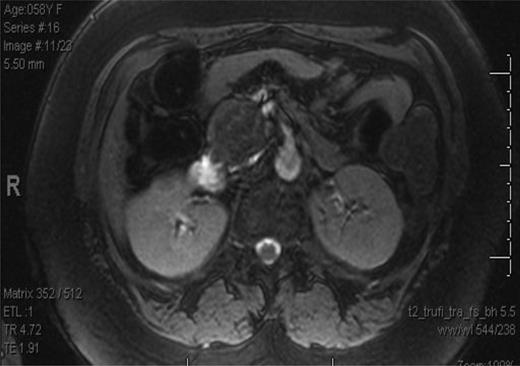

The patient is a 58-year-old African-American female who presented with several months of left lower quadrant pain. A computed tomography (CT) and magnetic resource imaging (MRI) of abdomen/pelvis demonstrated a 3.8-cm hyper vascular mass in the head of the pancreas without any evidence of distant metastasis or spread to the surrounding vasculature (Figs. 1 and 2). The differential diagnosis includes endocrine tumor, gastrointestinal stromal tumor, sarcoma, solid pseudo-papillary tumor, inflammatory pseudotumour/tumor forming autoimmune pancreatitis and SFT. An endoscopic ultrasound with fine-needle aspiration was nondiagnostic. The carcinoembryonic antigen (CEA) and cancer antigen 19-9 (CA 19-9) were both mildly elevated at 6.5 (nl range 0–5.0) and 39 (nl range 0–37), respectively. Functional endocrine hormone studies were significant only for a mildly elevated gastrin level of 214, but the insulin, glucagon and vasoactive intestinal peptide (VIP) levels were all within normal limits. Her review of symptoms was negative for jaundice or weight loss. A Whipple procedure was performed. The patient had an uncomplicated hospital course and was discharged Post-op Day 7. She is alive and well 2 years post-operatively.

MRI of the abdomen and pelvis showing mass in head of the pancreas.